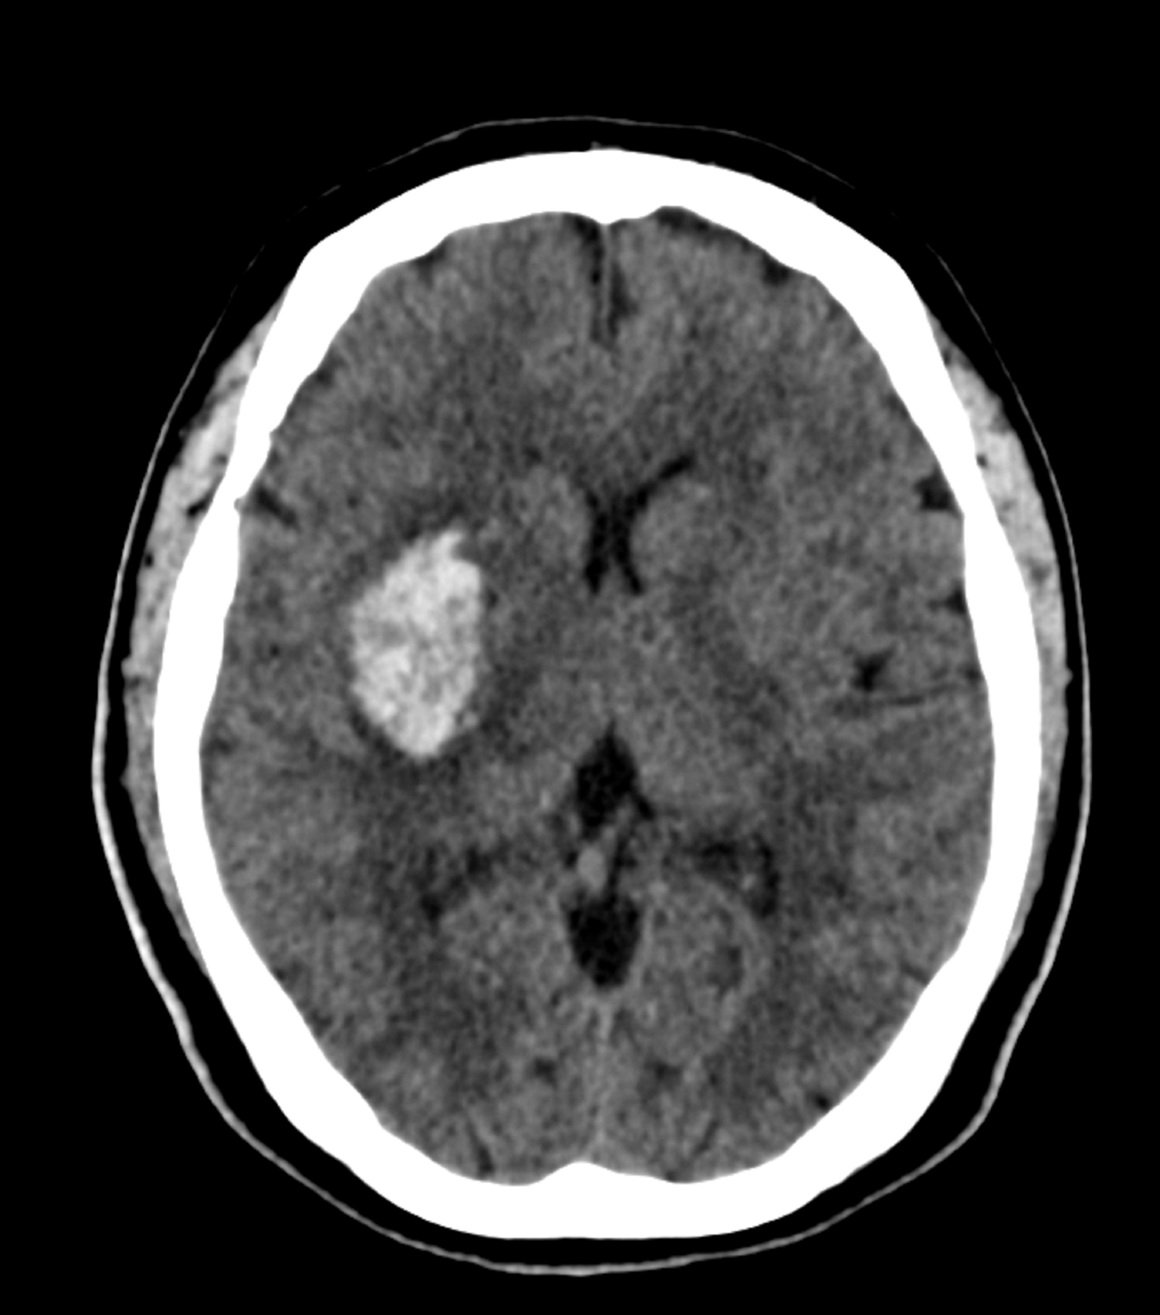

Krvarenje u mozgu, ili intracerebralna hemoragija, ozbiljno je stanje koje nastaje kada krvna žila u mozgu procuri ili pukne, uzrokujući pritisak na moždano tkivo.

Ako sumnjate na unutarnje krvarenje mozga, liječnici će napraviti:

- CT ili MRI snimke